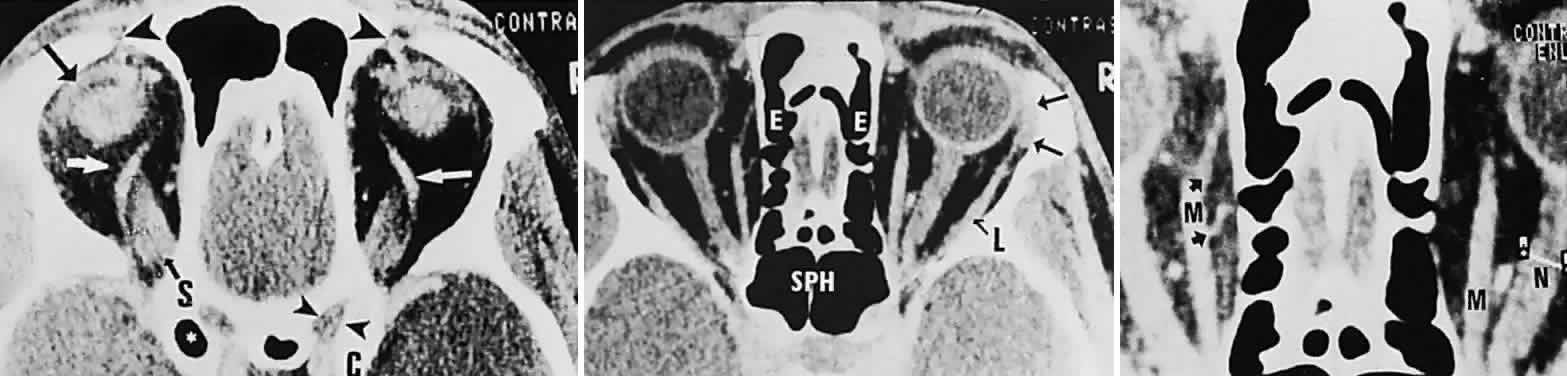

Computed tomography (CT) is presently the single most productive modality for analyzing orbital bones, with which the following structures may be visualized: the bony confines of the orbit and surrounding sinus structures; the lacrimal bony canal; the globe and lens; the intraorbital portions of the optic nerve; and the extraocular muscles, especially the horizontal and superior recti (Fig. 16). Moreover, CT with contrast enhancement discloses the full configuration and location of masses with respect to other orbital structures, principally the relationships to muscle cone, optic nerve, and lacrimal gland. In several particular instances, the location, configuration, and degree of contrast enhancement of lesions may strongly suggest a distinctive tumor type (Fig. 17) or inflammation (e.g., cavernous hemangioma, optic glioma, lacrimal gland tumor, dermoid cyst, mucocele, perioptic meningioma, single or multiple muscle thickening),65–67 but no firm histopathologic diagnosis may be inferred by CT characteristics alone.

Fig. 16. Contrast-enhanced CT scan of normal orbits. Top. Superior orbit section shows superior ophthalmic veins (white arrows), superior rectus origin (S), left levator muscle complex (black arrow), position of trochlea and tendon of superior oblique muscles (large arrowheads), right optic canal (small arrowheads), and anterior clinoid (C). (*, pneumatized left anterior clinoid.) Middle. Midorbital section shows ethmoidal sinus complex (E), sphenoidal sinus (SPH), lacrimal gland (arrows), and lateral rectus (L). Bottom. Enlargement shows left medial rectus (M), with anterior (top arrow) and posterior (bottom arrow) ethmoidal arteries; note cursor across optic nerve on right (N).